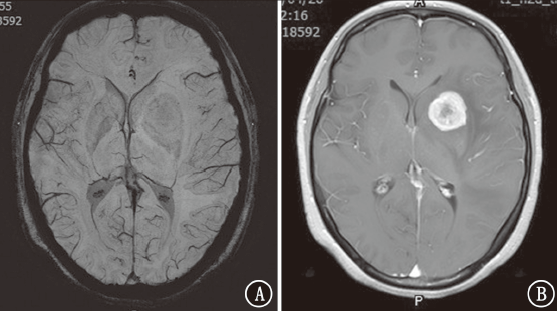

目的探讨磁敏感加权成像(SWI)在颅内转移瘤中的鉴别诊断价值。方法收集2018年 1月至2020年4月新疆维吾尔自治区人民医院住院患者中原发肿瘤为肺癌、乳腺癌、肾癌、直肠癌、膀胱癌、黑色素瘤的颅内转移瘤及胶质母细胞瘤患者63例,半定量评估肿瘤内的敏感性信号强度(ITSS)分级。比较颅内转移瘤与胶质母细胞瘤ITSS分级。结果81个颅内转移瘤中,0级为36个(44.4%),Ⅰ级为25个(30.9%),Ⅱ级为14个(17.3%),Ⅲ级为6个(7.4%);27个胶质母细胞瘤均为Ⅱ~Ⅲ级(100%)。肺癌转移瘤0~Ⅰ级占73.6%(28/38),乳腺癌转移瘤0级占84.6%(22/26),肾癌转移瘤Ⅱ级占5/6,直肠癌转移瘤0~Ⅰ级占4/5,胶质母细胞瘤Ⅲ级占77.8%(21/27)。颅内转移瘤与胶质母细胞瘤ITSS分级组间差异有统计学意义(Z=7.013,P<0.001)。采用受试者工作特征曲线分析显示,ITSS≤Ⅰ级判断颅内转移瘤的敏感性为100%,特异性为75.3%,曲线下面积为0.936(95%CI为0.891~0.980,P<0.001)。结论颅内转移瘤ITSS分级多表现为0~Ⅰ级,胶质母细胞瘤多表现为Ⅱ~Ⅲ级。SWI在颅内转移瘤中有一定的鉴别诊断价值。

ObjectiveTo explore the value of susceptibility weighted imaging (SWI) in differential diagnosis of intracranial metastatic tumors.MethodsSixty-three patients with intracranial metastatic tumors (primary tumors of lung cancer, breast cancer, kidney cancer, rectal cancer, bladder cancer and melanoma) and glioblastomas in People's Hospital of Xinjiang Uygur Autonomous Region from January 2018 to April 2020 were collected, and the intratumoral susceptibility signal intensity (ITSS) was evaluated semi-quantitatively. The grading characteristics of ITSS of metastatic tumors and glioblastomas were compared.ResultsAmong the 81 intracranial metastatic tumors, 36 (44.4%) were grade 0, 25 (30.9%) were grade Ⅰ, 14 (17.3%) were grade Ⅱ and 6 (7.4%) were grade Ⅲ. Among the 27 glioblastomas, 27 (100%) were grade Ⅱ-Ⅲ. Grade 0-Ⅰ metastatic tumors of lung cancer accounted for 73.6% (28/38). Grade 0 metastatic tumors of breast cancer accounted for 84.6% (22/26). Grade Ⅱ metastatic tumor of kidney cancer accounted for 5/6. Grade 0-Ⅰ metastatic tumors of rectal cancer accounted for 4/5. Grade Ⅲ glioblastomas accounted for 77.8% (21/27). The difference of ITSS classification between intracranial metastatic tumors and glioblastomas was statistically significant (Z=7.013,P<0.001). According to the receiver operating characteristic curve analysis, the sensitivity and specificity of ITSS ≤grade Ⅰ were 100% and 75.3% respectively, and the area under the curve was 0.936 (95%CI: 0.891-0.980,P<0.001).ConclusionThe patients with intracranial metastatic tumor usually present ITSS grade 0-Ⅰ, and the patients with glioblastoma usually present ITSS grade Ⅱ-Ⅲ. SWI has a certain value for differential diagnosis of intracranial metastatic tumors.